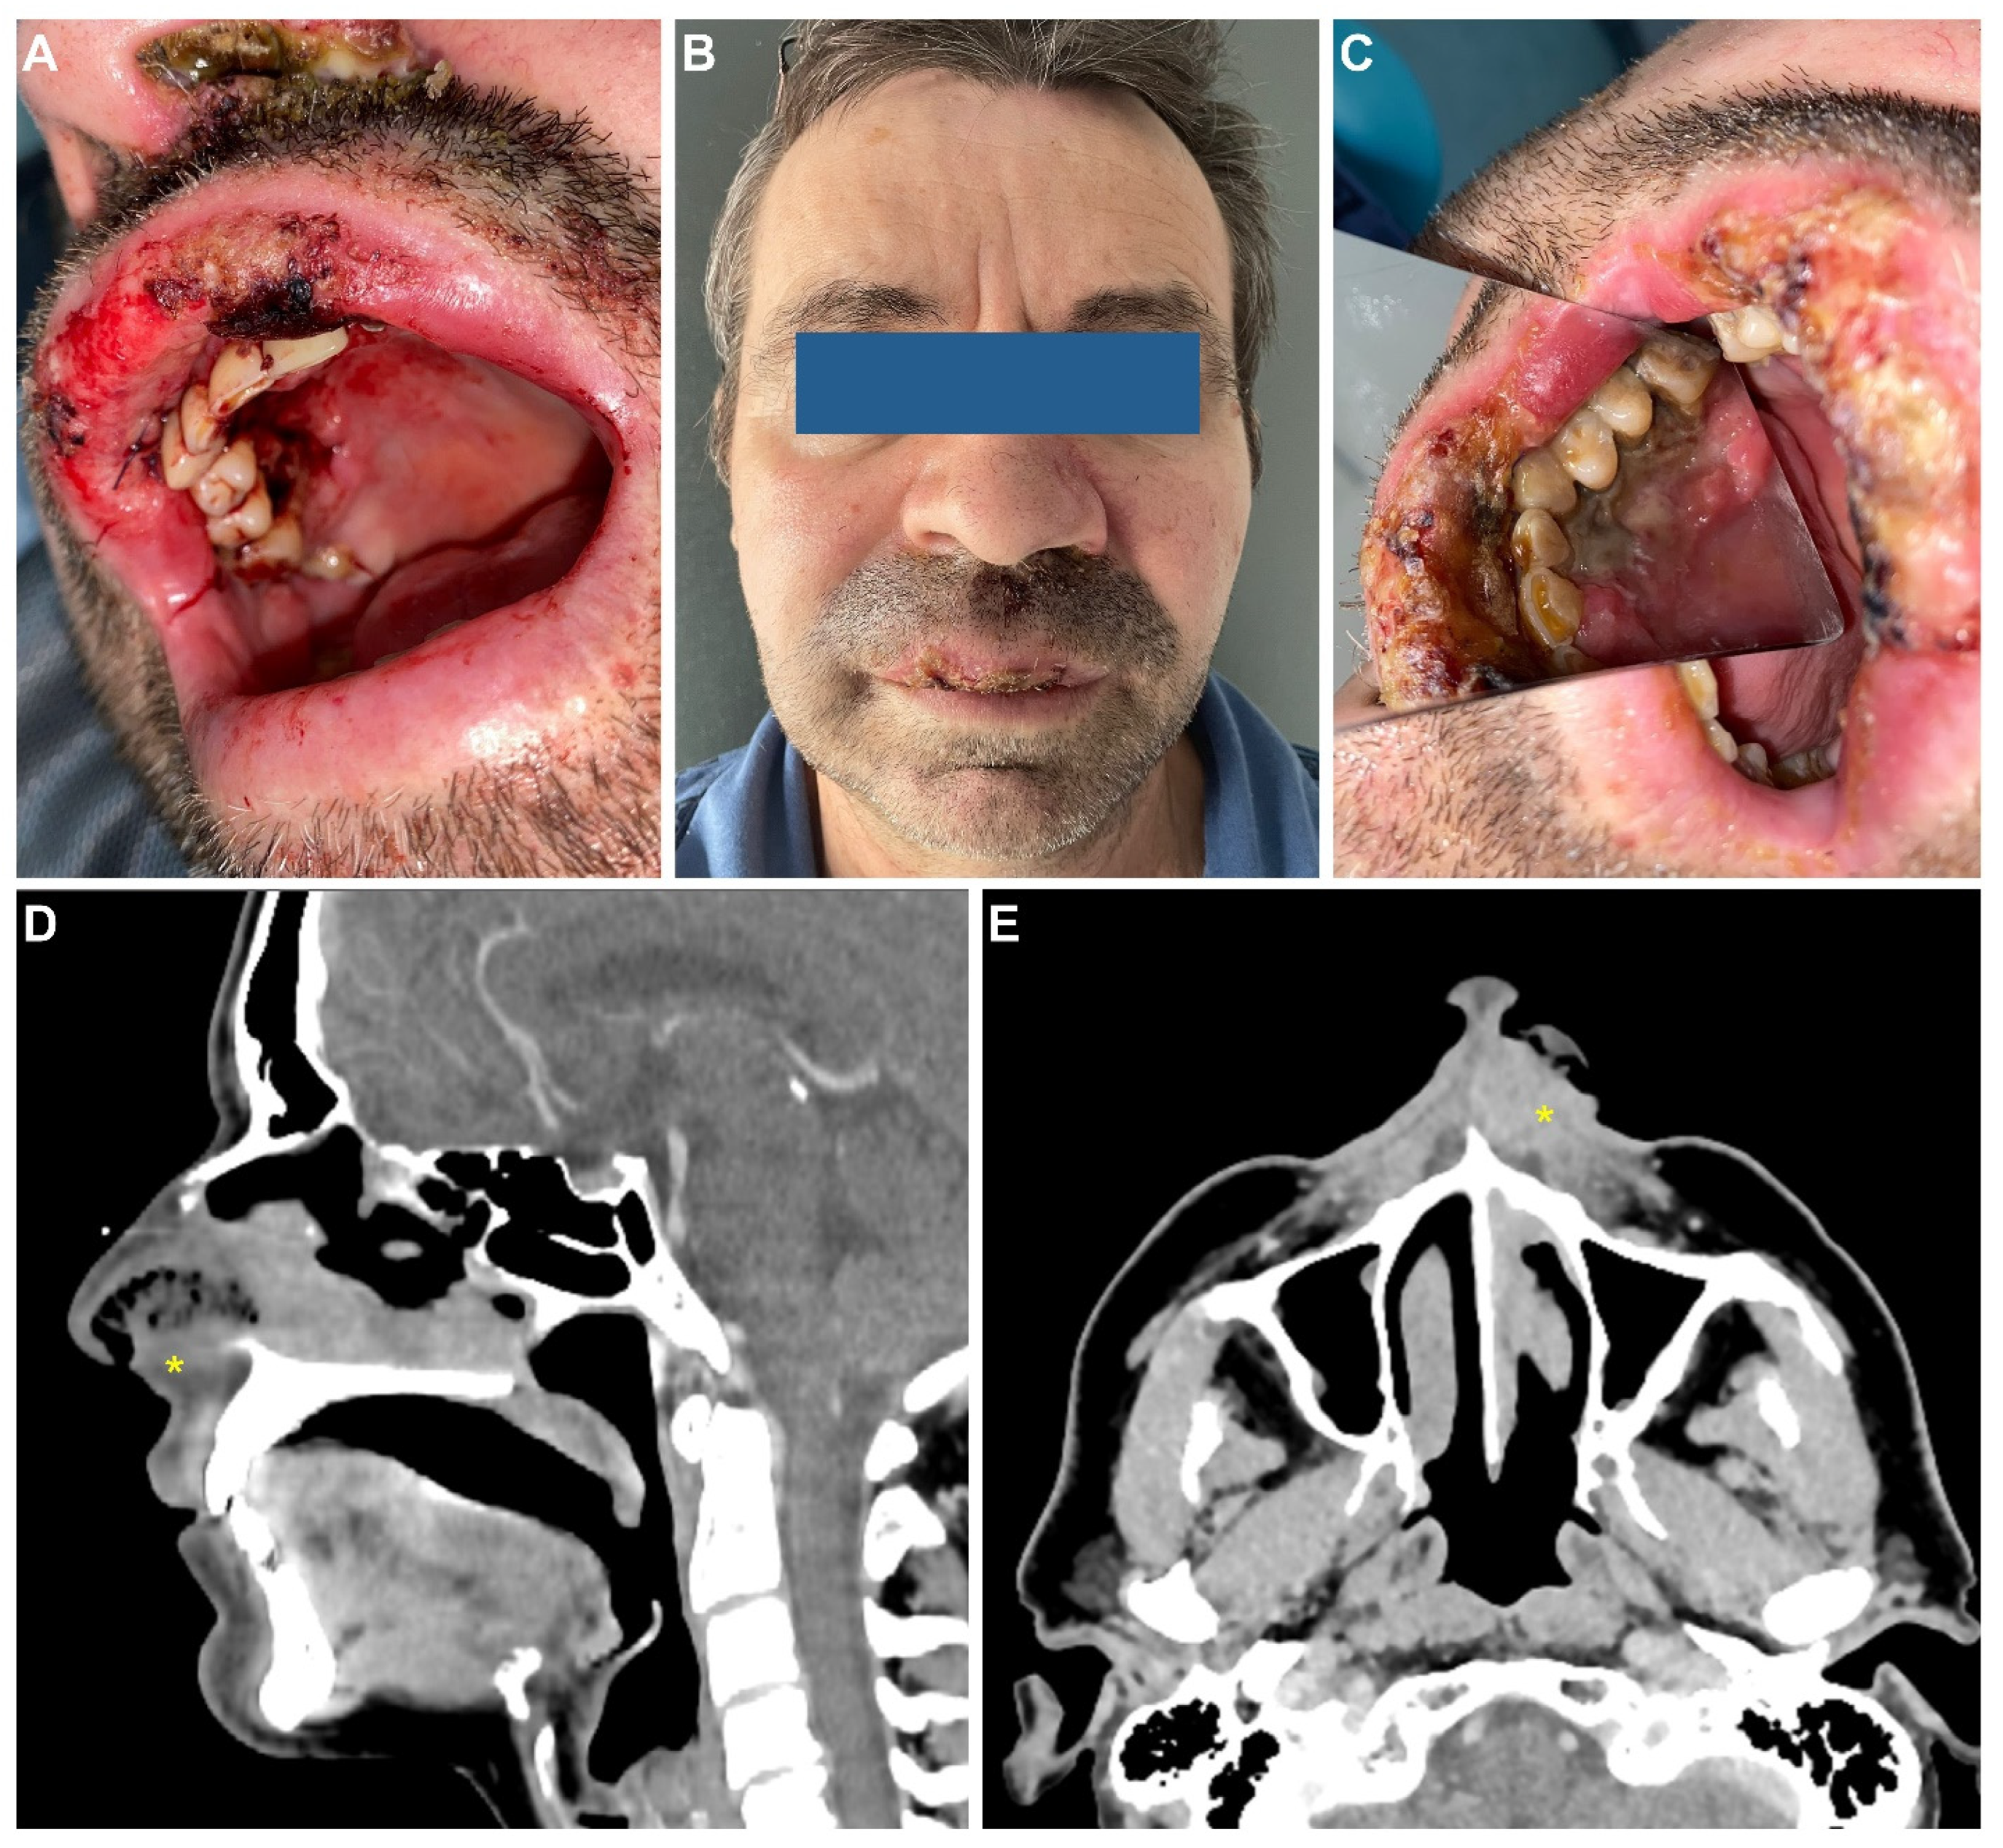

2. Case Report